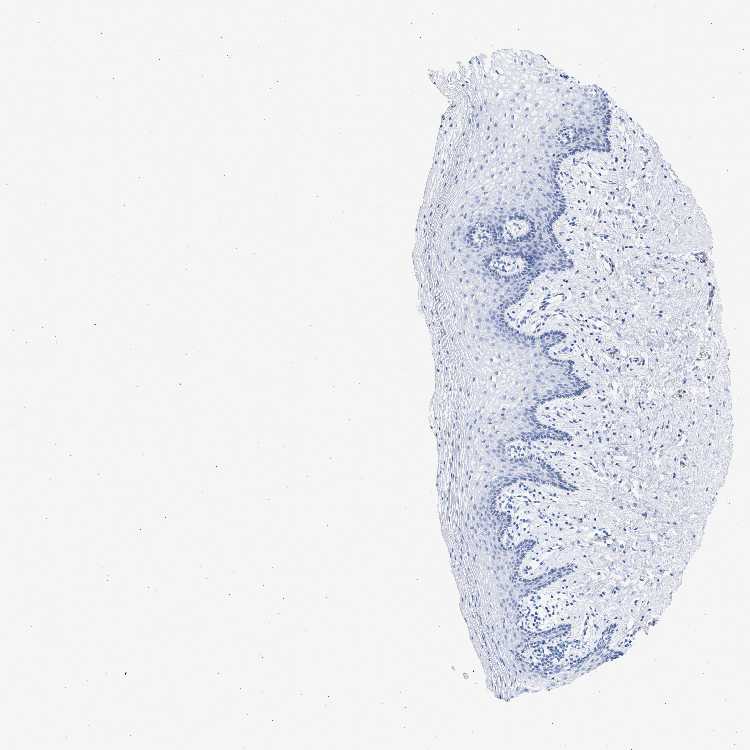

VAGINA - Antibody stainingi

Antibody staining in the annotated cell types in the current human tissue is reported as not detected, low, medium, or high, based on conventional immunohistochemistry profiling in selected tissues. This score is based on the combination of the staining intensity and fraction of stained cells.

Each image is clickable and will lead to virtual microscopy that enables deeper exploration of all samples and also displays staining intensity scores, fraction scores and subcellular localization as well as patient and tissue information for each sample.

Antibody HPA016816Antibody HPA017382

Squamous epithelial cells Not detectedNot detected